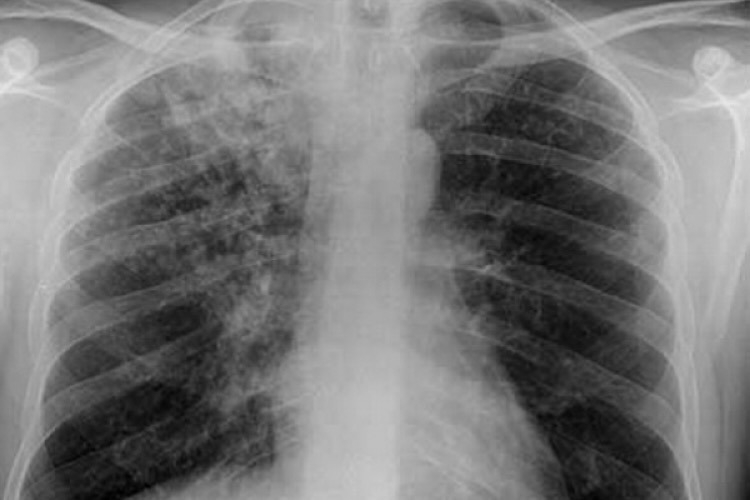

В Республике Молдова будут внедрены новые технологии диагностики туберкулеза, в том числе будут использованы портативные и мобильные радиологические установки, оснащенные программами, которые обеспечивают быстрый результат в течение примерно трех минут, чтобы люди с подозрением на туберкулез могли пройти дальнейшее обследование. Об этом сообщила координатор Национальной программы реагирования на туберкулез Валентина Вилк на пресс-конференции, состоявшейся по случаю Всемирного дня борьбы против туберкулеза, передает IPN.